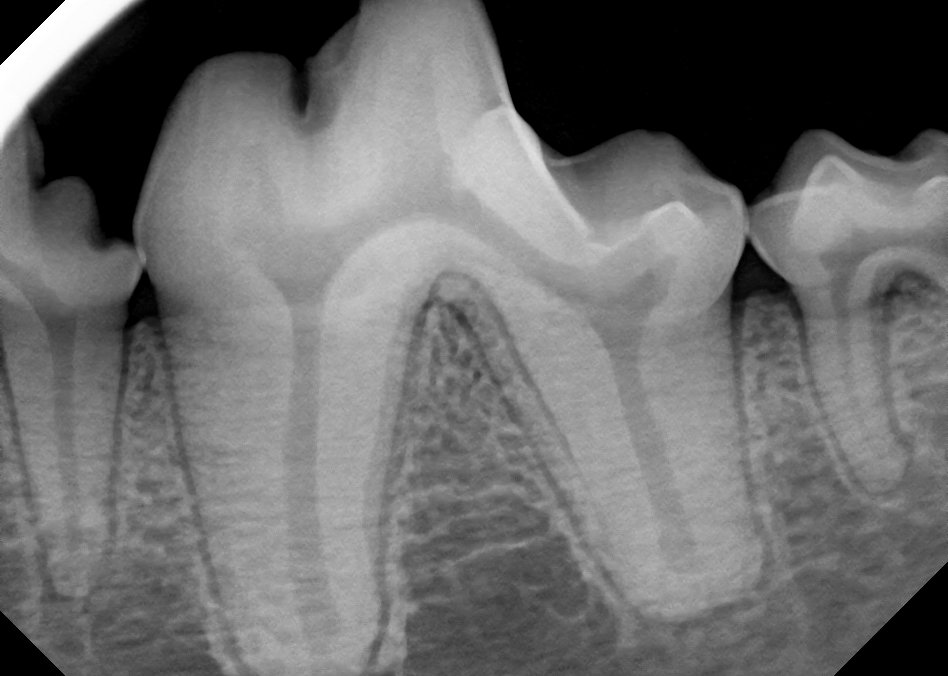

Dental Radiograph